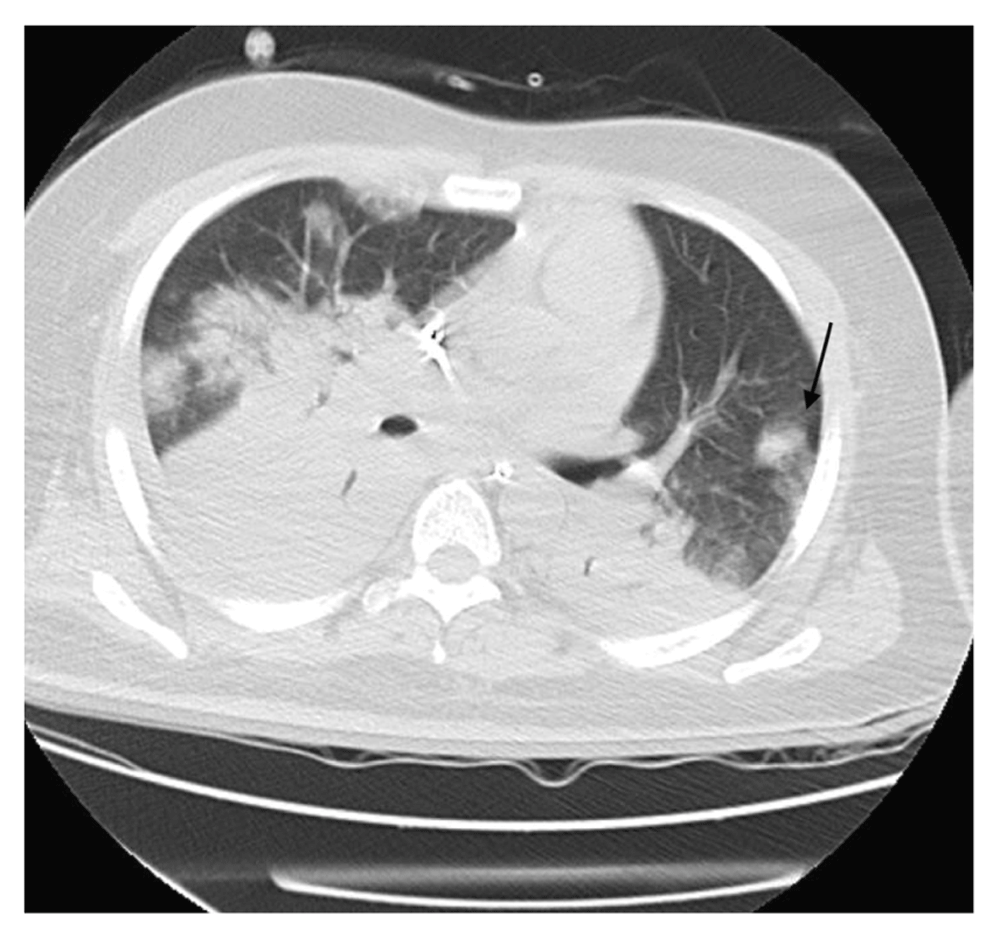

The patient was started on continuous renal replacement therapy (CRRT); his clinical status deteriorated with increased ventilation requirement of FiO2 50% to 80%, PEEP 8 to 16 cm H2O on day 4. A chest X-ray showed multiple bilateral ill-defined patchy opacities in the right lower lung zone (Figure 1). A computed tomography (CT) scan for his chest was done and showed multiple bilateral patchy ground-glass opacities (Figure 2, Figure 3). Bilateral lower lobe consolidations with air bronchogram showed greater involvement of the right lower lobe, while an unenhanced CT of the brain demonstrated hyperdense foci seen in the left inferior frontal, right parietal lobes with surrounding edema, and right central sulcus compatible with intra-parenchymal hemorrhage and subarachnoid hemorrhage, respectively. A follow-up MRI of the brain was obtained, showing an increased gyral pattern of T1 and FLAIR sequence, as observed in the bilateral occipital, bilateral frontal, and right parietal lobes, likely related to laminar necrosis from the anoxic- ischemic event. Gradient recalled echo (GRE) sequence showed scattered areas of blooming artifacts that are likely to be related to recent extensive hemorrhage. The brain findings were suggestive of hemorrhage and hypoxic injuries of vascular causes of previous cardiac arrest events.

The scan shows a left lower lobe nodule (arrow) with surrounding faint ground-glass densities giving halo sign appearance.